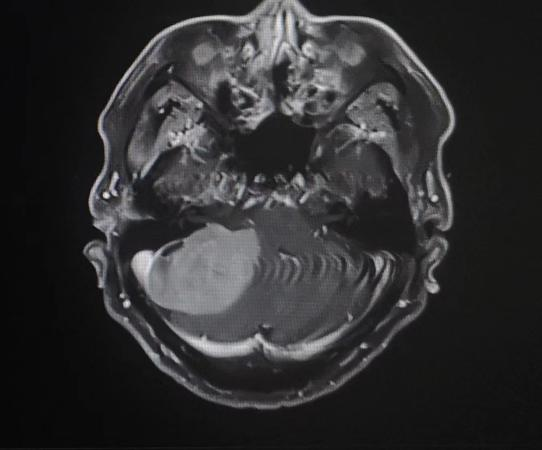

患者入院后,头颅MR检查后发现,小脑右侧长了巨大肿瘤,直径约6公分,患者家属收到不小的惊吓。患者4年前曾做过一次头颅核磁共振,当时肿瘤较小,考虑到患者已经88岁,家人还是决定保守观察,没想到如今,它已经长大到足足有一个土豆那么大,而且患者头晕较重,反复恶心、呕吐,卧床不起,因此必须进行手术,才能解决患者病症。

患者家属反复考虑、综合思量后,决定接受手术治疗。神经外科二病区主任白西民及团队进行综合评估,术前讨论,研究患者肿瘤位置、毗邻关系及心肺状况,制定周密手术方案。联合呼吸科、心内科、麻醉科及重症医学科等学科会诊,研究制定详细手术方案及应急预案。